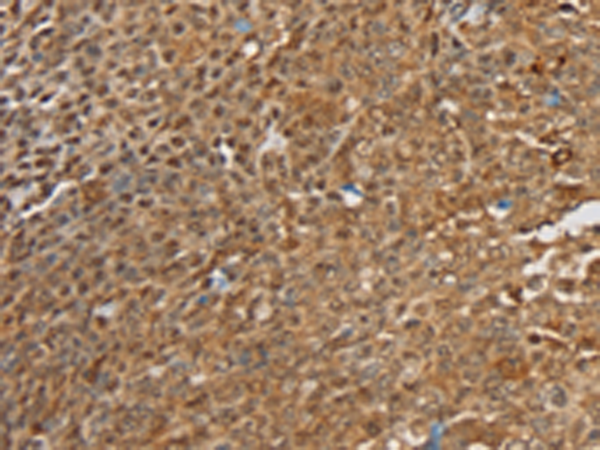

分类: 科研抗体货号: P12174别名: SIR2L4应用: IHC反应种属: Human, Mouse